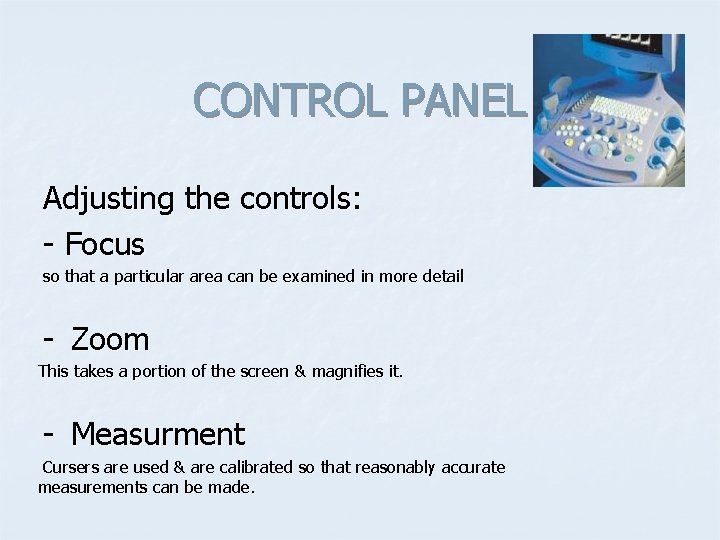

CONTROL PANEL Adjusting the controls: - Focus so that a particular area can be examined in more detail - Zoom This takes a portion of the screen & magnifies it. - Measurment Cursers are used & are calibrated so that reasonably accurate measurements can be made.

CONTROL PANEL Adjusting the controls: - Taking pictures & labelling Images are of value as aid memoirs and for demonstration and discussion. Attension please !!! Any conclusions should be drawn while actually scanning the patient.